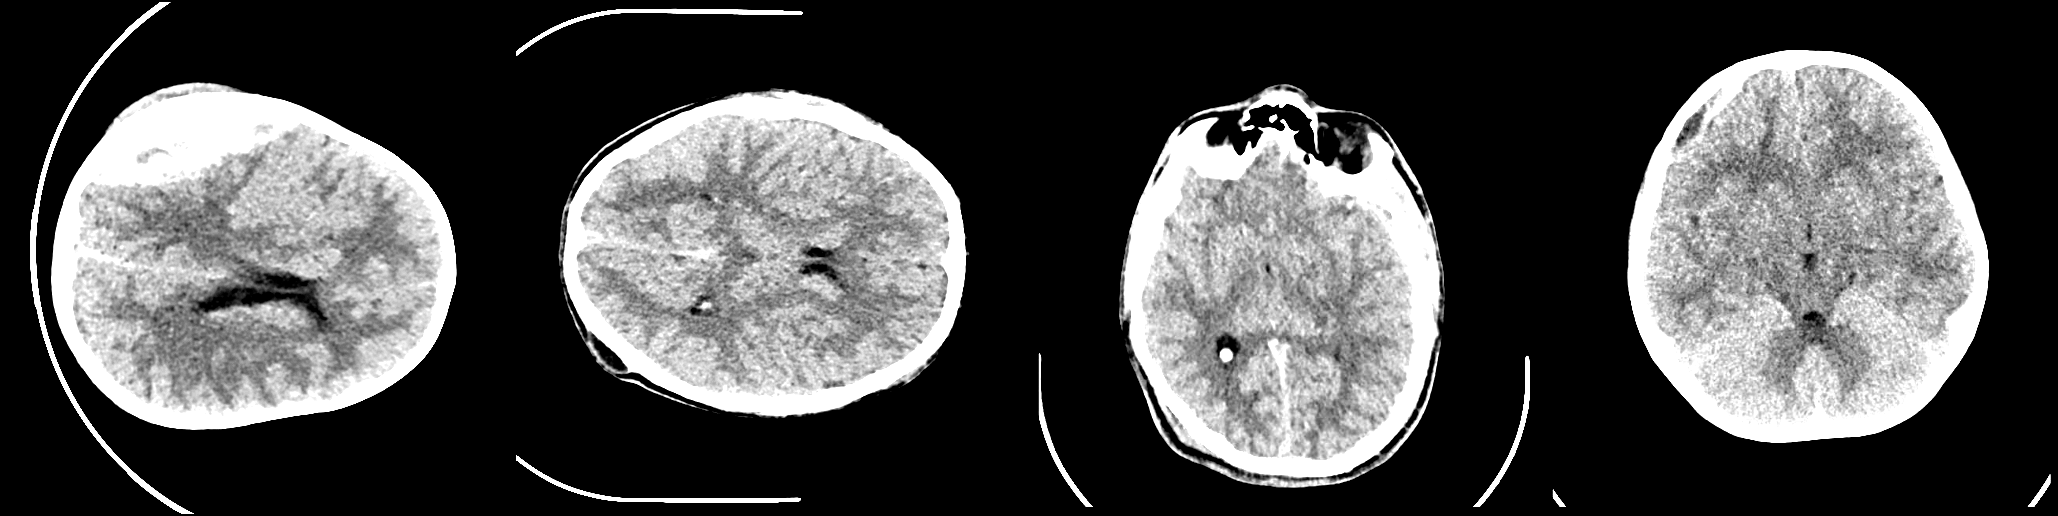

A publicly available dataset [6] containing 82 CT scans were utilised for this study. The dataset includes 36 scans of patients diagnosed with intracranial haemorrhages of types Subarachnoid, Epidural, Intraventricular, Subdural and Intraparenchymal. Approximately 30 slices of 5 mm thickness are used for each CT scan. The mean and standard deviation of the age of the patients were 27.8 and 19.5, respectively. 46 of the patients were male, and 36 were female. Two senior radiologists segmented each slice of all non-contrast CT scans for different brain haemorrhages. The radiologists had no access to the historical clinical records of patients. Intra-cranial regions were delineated in each CT slice by the radiologists. Siemens Medical Solutions syngo was first used to process the CT DICOM files. Two videos were saved (avi format) using bone and brain windows. Gray Scale 650X650 images (jpg format) were finally produced for the brain window. Examples of CT scan slices and corresponding segmentation masks are shown in figures 1,2 respectively.

Refer to caption

Figure 1: Images of Brain haemorrhage CT-Scan Slices